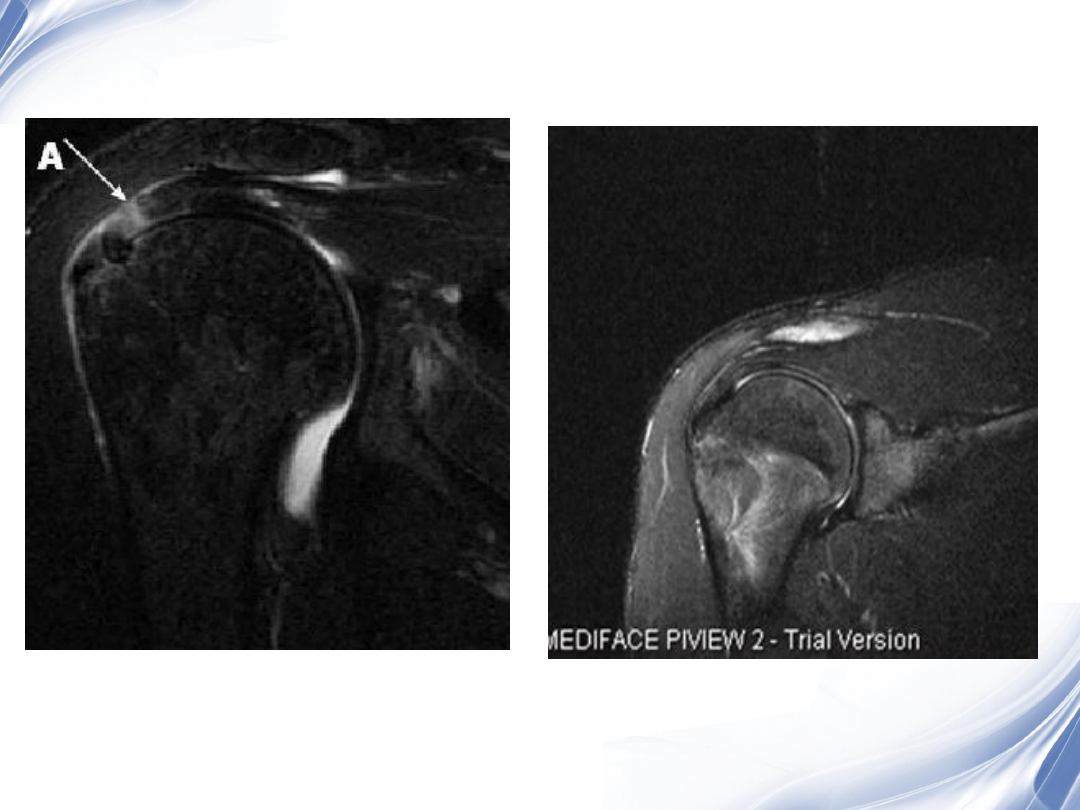

34

肩袖全层撕裂

正常MRI

background image

35